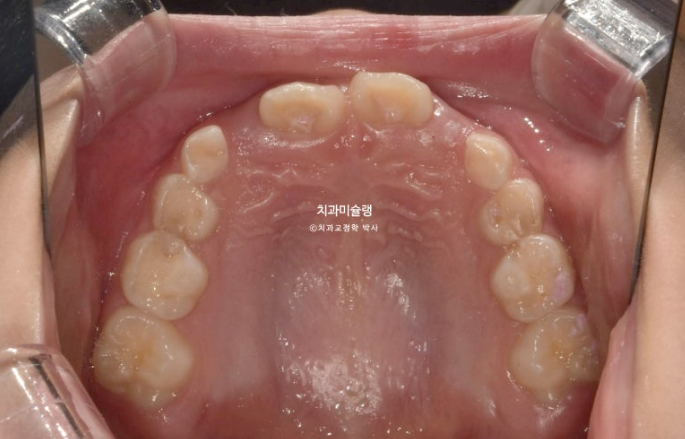

23.10~25.08